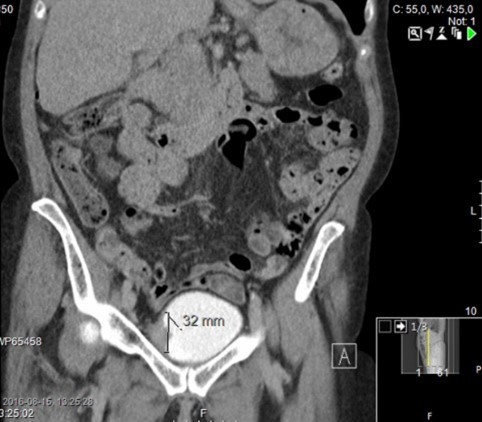

Förmodad urinblåsetumör

Vad ser du?

Vad är detta?

Cancer i urinblåsa (urotel)